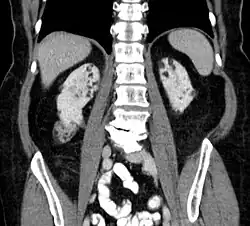

Computed tomography showing multiple angiomyolipomas of the kidney in a patient with lung lymphangioleiomyomatosis on CT: suspected TSC

Between 26% and 80% of TSC patients have benign tumors of the kidneys called angiomyolipomas, with hematuria being the most frequent presenting symptom.[8] TSC angiomyolipomas differ from non-TSC angiomyolipomas in age of presentation (31.5 years vs 53.6 years), mean tumor size (8.2 cm vs 4.5 cm), and percentage of cases requiring surgical intervention (50% vs 28%).[8] Although benign, an angiomyolipoma larger than 4 cm is at risk for a potentially catastrophic hemorrhage, either spontaneously or with minimal trauma.